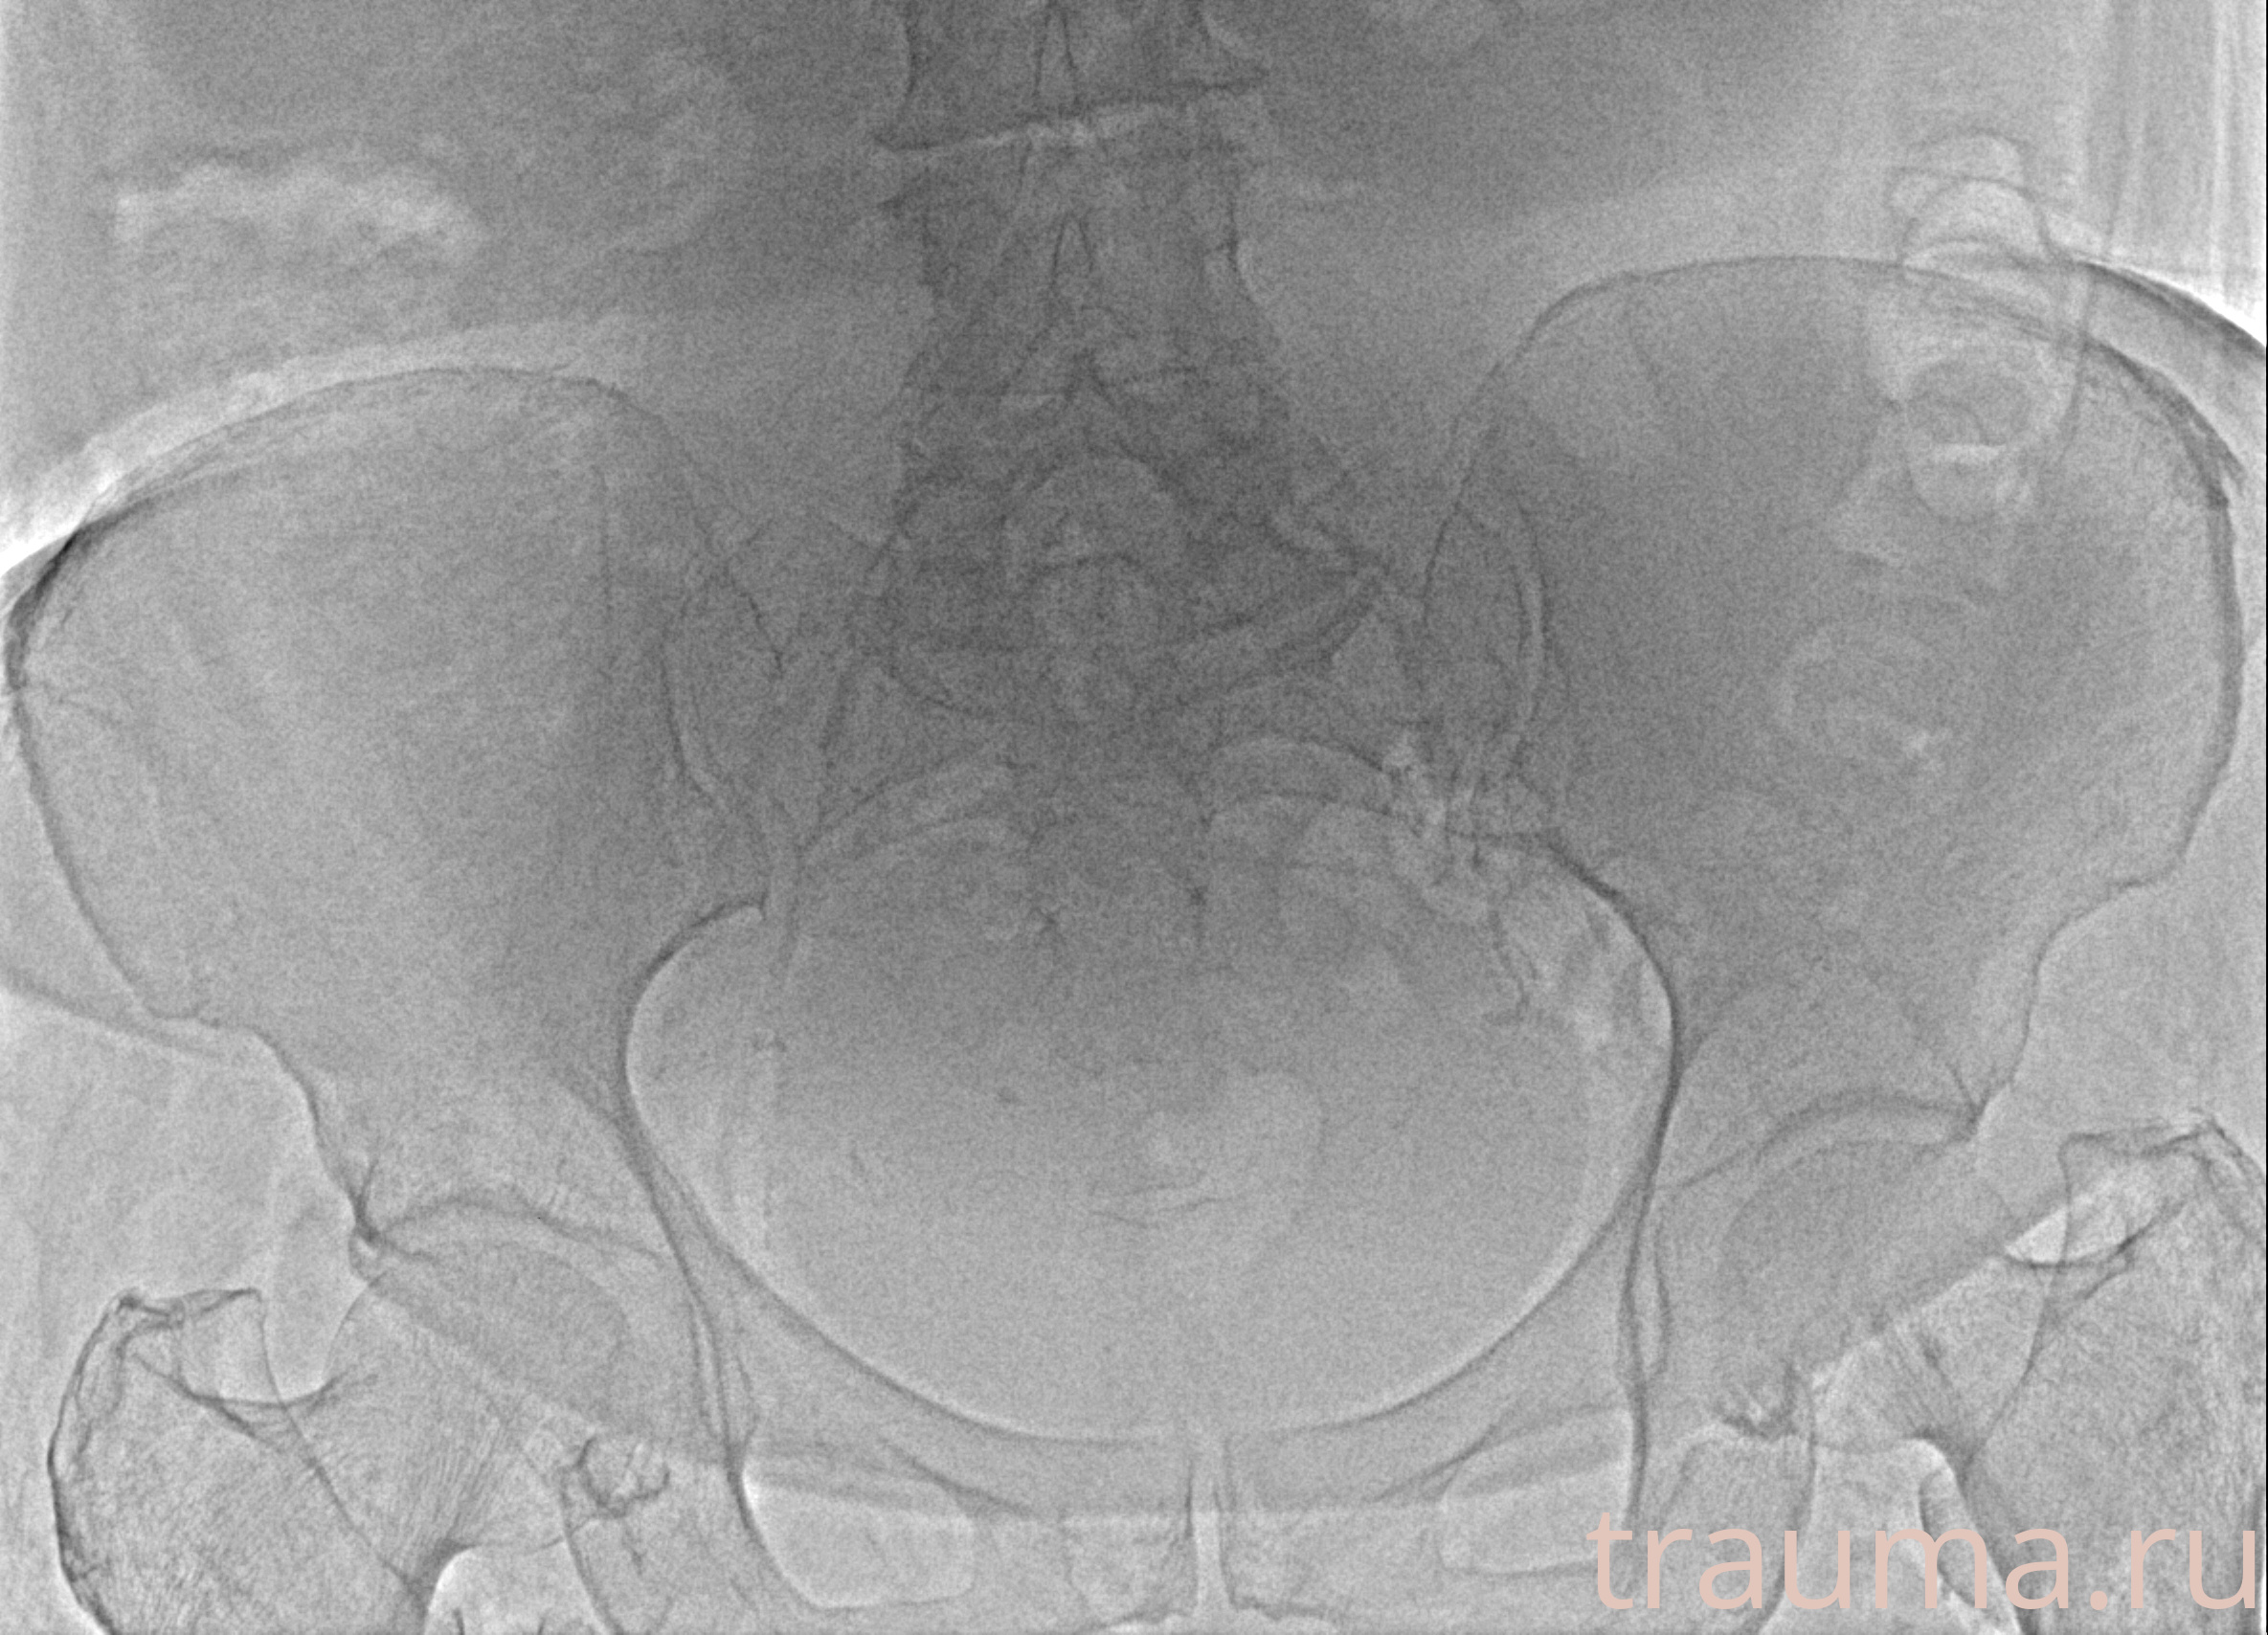

Рентгенограммы

Рентген на дому: по вашему адресу приезжает врач-рентгенолог, травматолог-ортопед с мобильным рентгеновским аппаратом, проводит диагностику травмы или заболевания, делает необходимые рентгенограммы, дает рекомендации по дальнейшему лечению. Получить качественные снимки в домашних условиях возможно благодаря уникальной методике, разработанной МосРентген Центром для института  Склифосовского